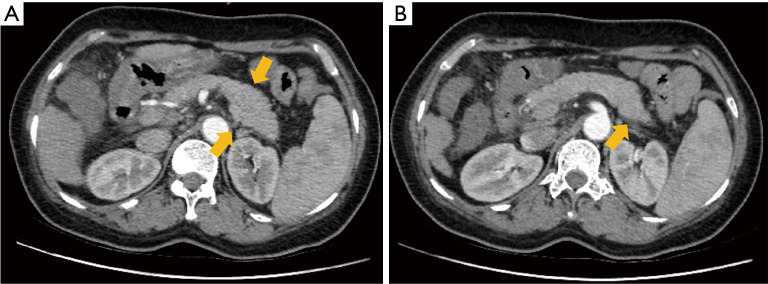

Case description: This case report presents two patients with AP, where a mismatch was observed between clinical and imaging severity assessments. In the first case, laboratory tests suggested mild AP, while computed tomography (CT) imaging indicated severe pathology. In contrast, the second case showed severe AP according to the Acute Physiology and Chronic Health Evaluation II (APACHE II) score, but the CT imaging only revealed mild findings. This clinical-CT mismatch highlights the need for a comprehensive approach to evaluating AP severity, rather than relying on a single assessment method.